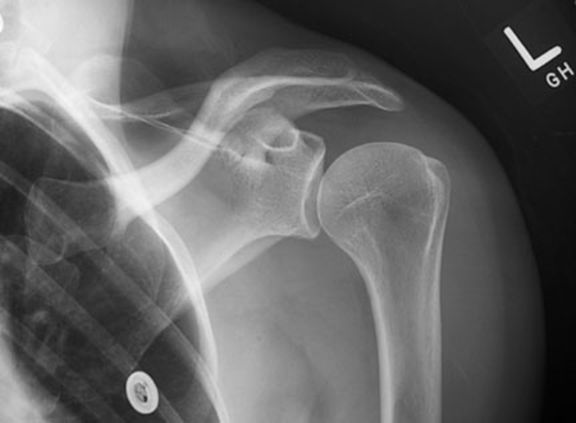

正常肩关节

肩锁关节脱位

肱骨外科颈骨折

内收或外展型损伤–最常见–骨折线为横行,伸展型损伤–间接外力引起–骨折线横行,向前成角,屈曲型损伤:较少见。